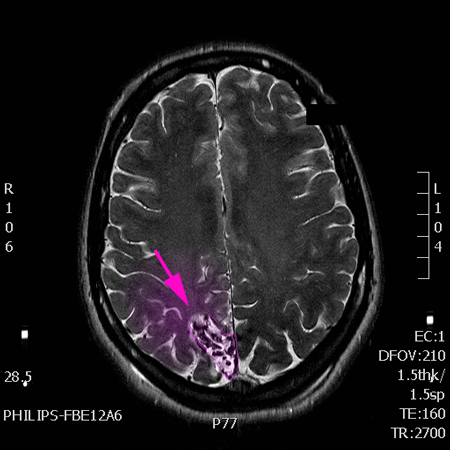

Αρτηριοφλεβώδεις Δυσπλασίες:

Μαγνητική ή αξονική τομογραφία εγκεφάλου με σκιαγραφικό,

Μαγνητική, αξονική ή, κυρίως, ψηφιακή αγγειογραφία εγκεφάλου.

AVM3

Αρτηριοφλεβώδης δυσπλασία, μάζα παθολογικών αγγείων με χρώμα